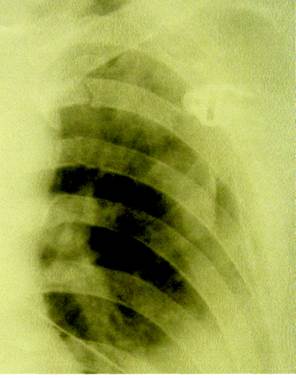

Рис. 5 Рентгенограмма при множественных переломах ребер.

Рис. 6 Реберное окно.